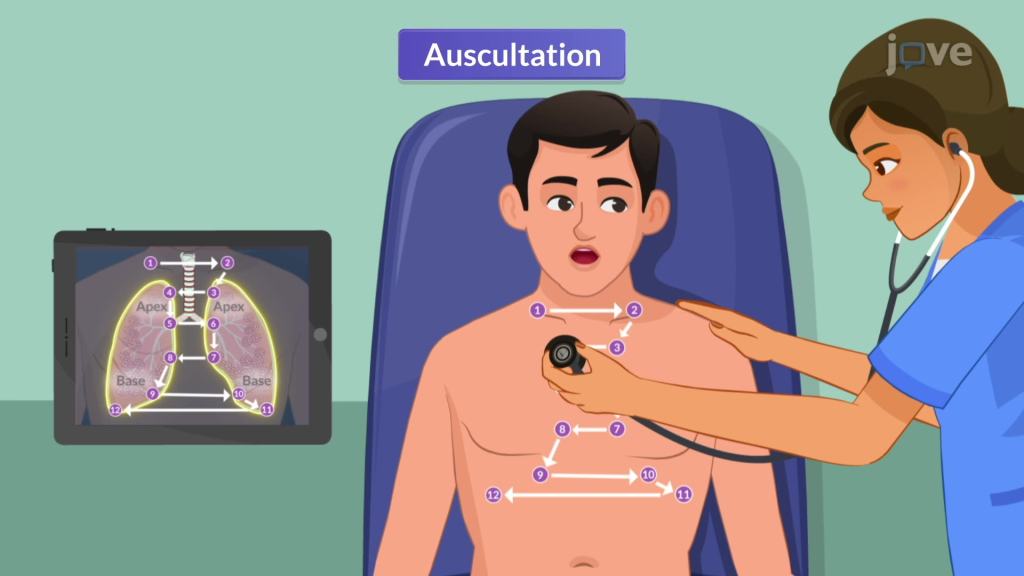

Auscultation (અસ્કલટેશન):

- અસ્કલટેશનમાં સ્ટેથોસ્કોપની મદદથી લંગ સાઉન્ડ સાંભળવામાં આવે છે.

- અસ્કલટેશન એક્સપર્ટ સ્ટાફ દ્વારા કરવામાં આવે છે.

- સ્ટેથોસ્કોપની મદદથી નોર્મલ લંગ સાઉન્ડની કેરેક્ટરિસ્ટિક નોટ કરવી જેમ કે લોકેશન, ક્વોલિટી, ઇન્ટેન્સિટી

- આ ઉપરાંત કોઈપણ પ્રકારના એબનોર્મલ લંગ સાઉન્ડ સાંભળવા મળે છે કે નહીં તે અસ્કલટેટ કરવું.

- અસ્કલટેશનમાં ચેસ્ટની એન્ટેરિયર અને પોસ્ટેરીયર બાજુ ડાયાફ્રામની મદદથી લંગ સાઉન્ડ અસ્કલટેટ કરવામાં આવે છે. નીચે આપેલા પિક્ચરમાં દર્શાવ્યા મુજબ ચેસ્ટને અસ્કલટેટ કરવામાં આવે છે.

- ઇન્સ્પિરેશન અને એક્સપિરેશન બંને સમયે સાઉન્ડ નોટ કરવામાં આવે છે. વચ્ચે પેશન્ટને રેસ્ટ આપવામાં આવે છે જેથી હાઇપરવેન્ટિલેશનની કન્ડિશનની પ્રિવેન્ટ કરી શકાય.

- આમ અસ્કલટેશનની મદદથી એબનોર્મલ સાઉન્ડને ડિટેક્ટ કરવામાં આવે છે.

- આ ઉપરાંત અસ્કલટેશનમાં વોઇસ સાઉન્ડ (બ્રોન્કોફોની, ઇગોફોની) પણ નોટ કરવામાં આવે છે.